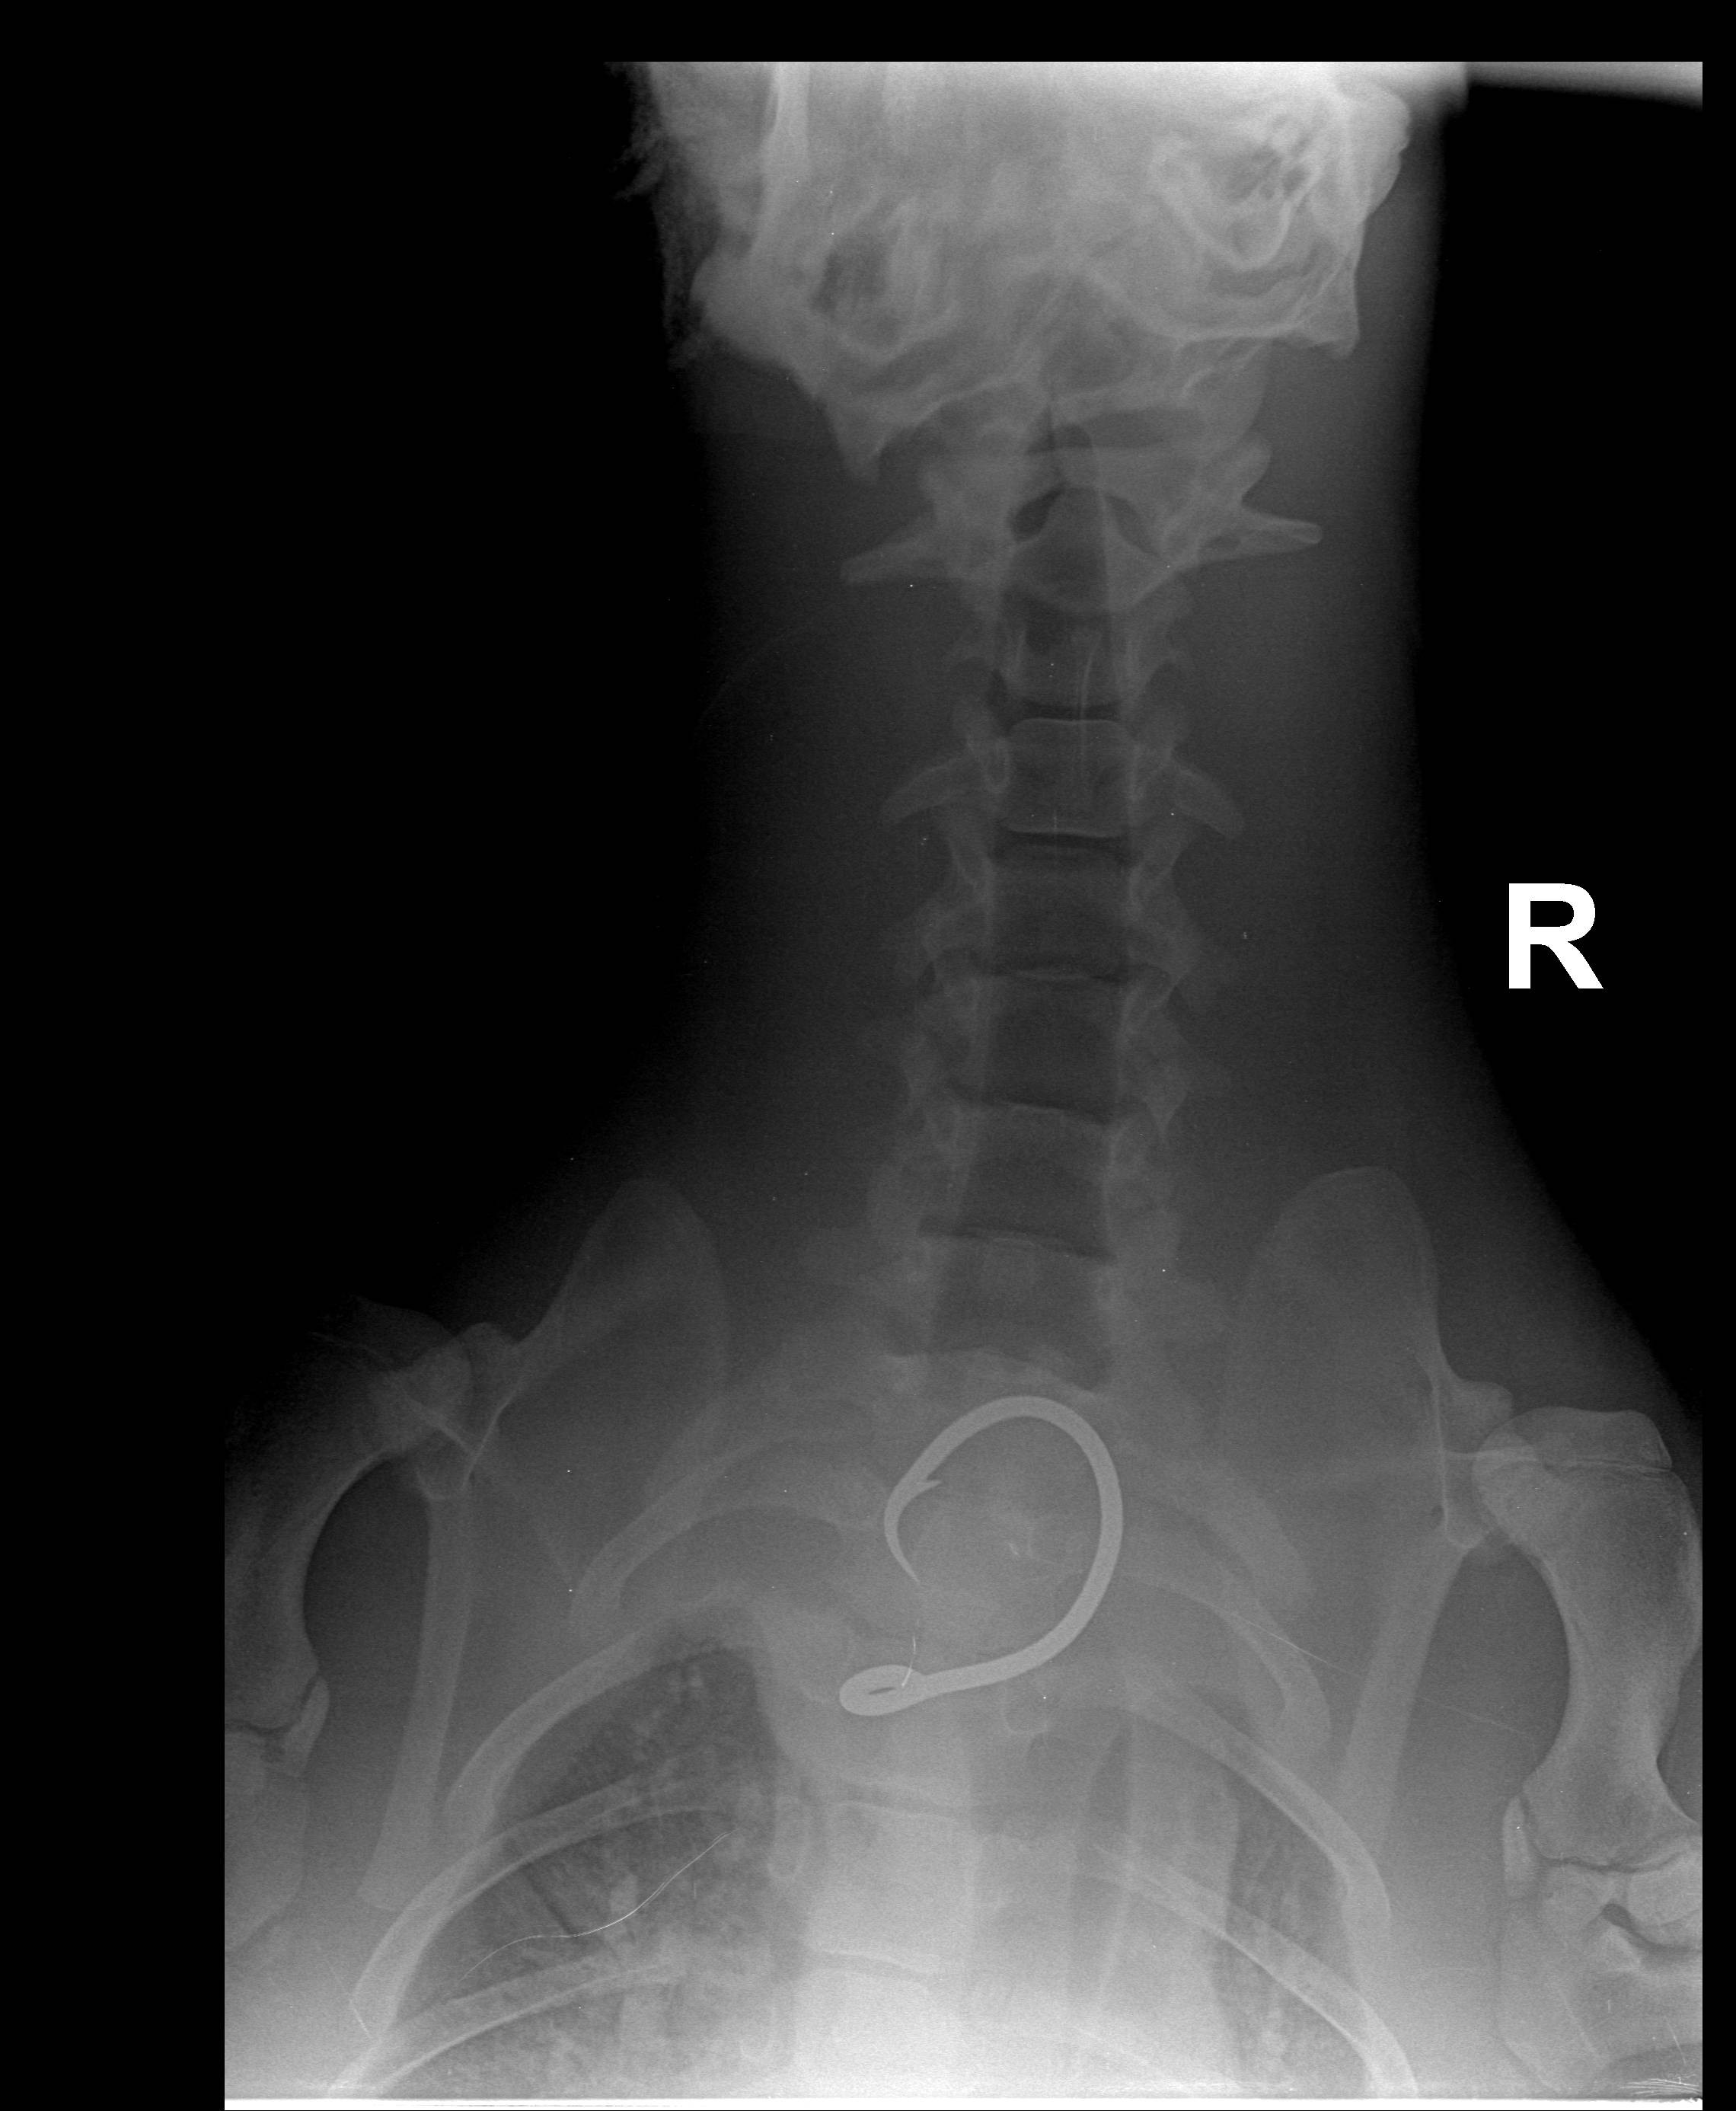

HONOLULU — The Department of Land and Natural Resources (DLNR) and the National Oceanic and Atmospheric Administration (NOAA) this morning reported that a juvenile monk seal flown by the U.S. Coast Guard from Hawai‘i Island to O‘ahu last Friday for medical treatment has died. A necropsy conducted by NOAA Fisheries revealed that the young male seal, known by his ID tags as RK68, suffered fractured ribs earlier in life, but ingestion of a fishing hook more recently is believed to be the cause of death.

Results of the necropsy reveal that the seal may have been hooked for several weeks or months. Officials believe had they received a detailed report of the hooking incident when it occurred, the chances of a life-saving response could have been much greater.